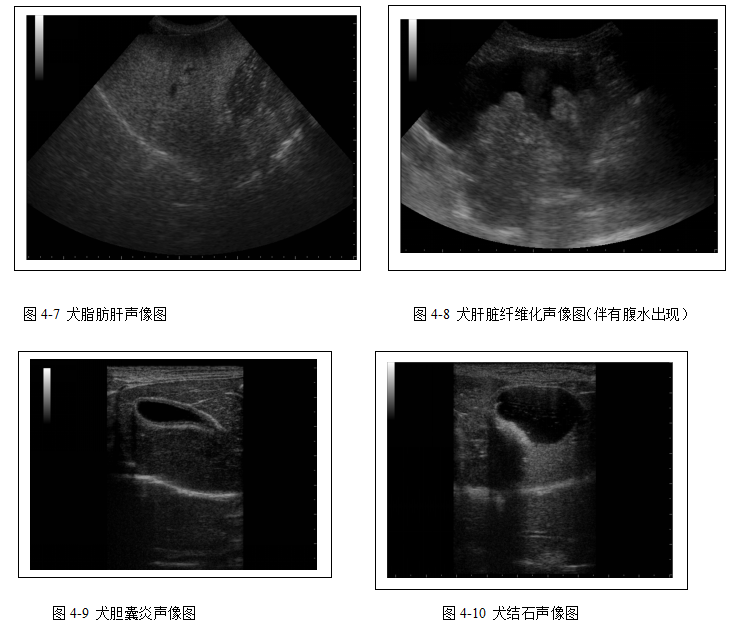

消化系统超声检查主要用于评估肝胆疾病(图4-7、4-8、4-9、4-10、4-11)和脾脏病变(4-12、4-13)。胰腺、胃肠道扫查在本教材中未涉及。